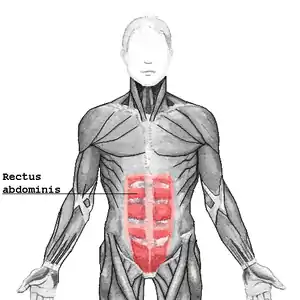

| Rectus abdominis muscle |

A rectus sheath hematoma is an accumulation of blood in the sheath of the rectus abdominis muscle. It causes abdominal pain with or without a mass.